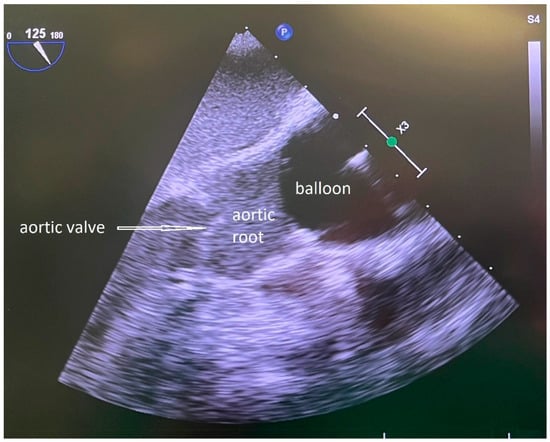

Figure 2. TOE control of the filled balloon of the IntraClude® device placed in the ascending aorta. Tip of the arrow pointing to the aortic valve.

2.5. Endoclamp

An arterial sheath (16 Fr Adelante® MAGNUM, Oscor Inc., Palm Harbor, CA, USA) was inserted percutaneously via the left common femoral artery to gain access for the IntraClude® device, a 10.5 Fr (3.5 mm), triple-lumen, 100 cm long catheter (Figure 1). Guided by TOE, the balloon of the IntraClude® device was placed in the ascending aorta above the coronary ostia. After opening the pericardium, inspection of the coronary vessels was performed, with the identification of the target vessels and an epicardial pacer was placed on the diaphragmatic side of the heart. After electrical induction of ventricular fibrillation, the balloon was gradually filled with saline until the aorta was occluded (Figure 2). During this critical part of the operation, care was taken that the pressure remained identical in the left and right arterial pressure line, in order to ensure that the balloon was placed proximally from the Truncus brachicephalicus and did not occlude, or partially compromise cerebral perfusion. During the inflation of the balloon TEE was performed, carefully inspecting the distance between the aortic valve and the endo-clamp balloon, the tip of the balloon being preferably placed at a distance of 2–3 cm from the aortic valve, leaving the aortic bulb free. In order to confirm complete occlusion of the ascending aorta, two parameters were used: the pressure of the aortic root, proximally from the inflated balloon, and the pressure in the balloon (preferably higher than 400 mmHg). Total occlusion was achieved in the moment the pressure in the aortic root dropped significantly compared to the systemic blood pressure. TEE and bilateral pressure monitoring were routinely used during the whole procedure, in order to immediately identify a potential dislocation or rupture of the endo-clamp balloon.